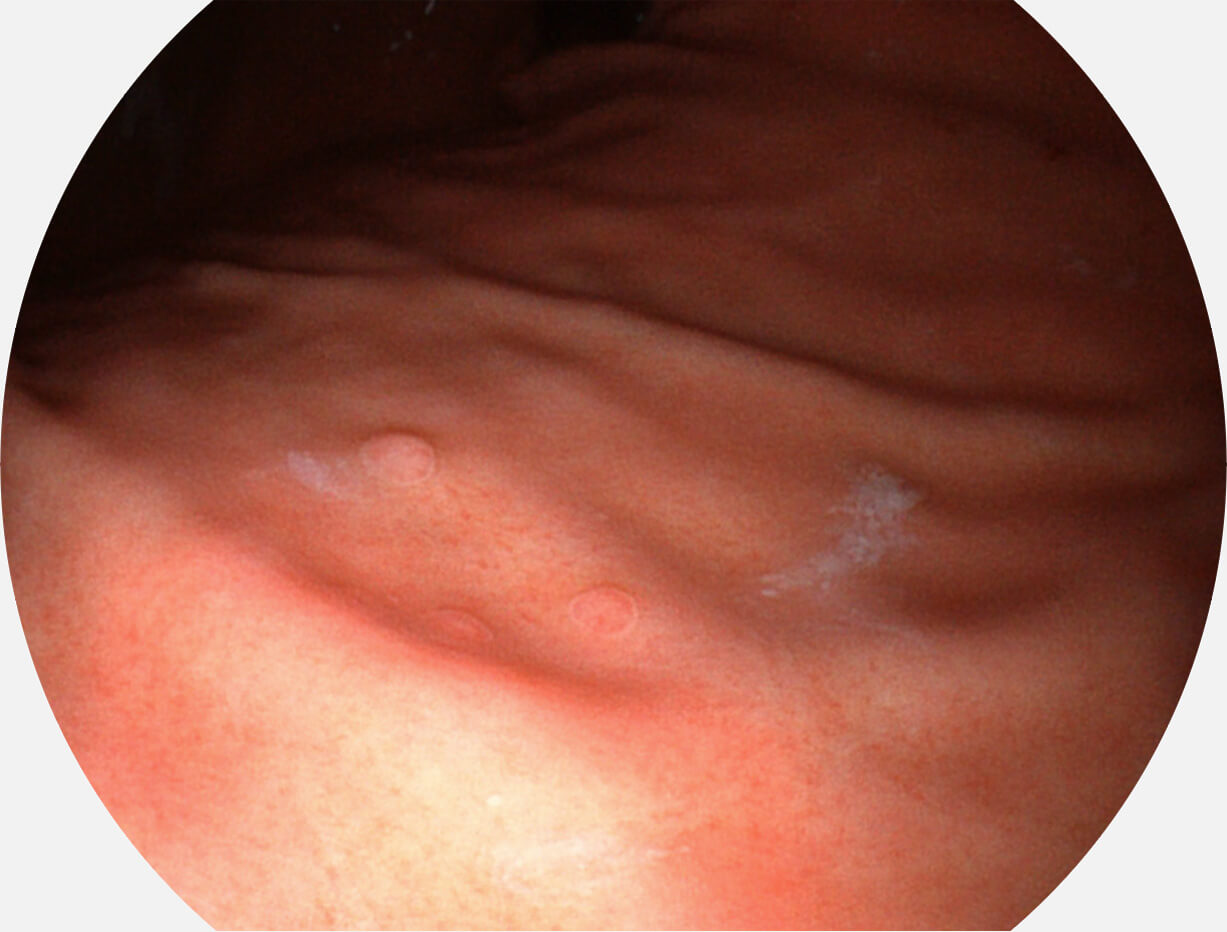

Versatile Intelligent Staining Technology, VIST

强调浅层黏膜结构的同时,保证照明亮度和提升浅层微血管与中层血管颜色对比度,病变边界更清晰。

VIST图像